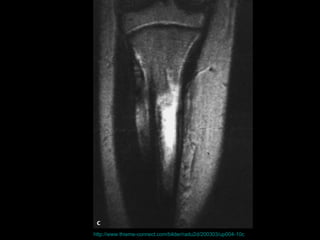

壓力性骨折 Stress Fracture 疲勞骨折 Fatigue fracture   骨質不良性骨折 Insufficiency fracture http://www.emedicine.com/radio/topic783.htm

http://www.thieme-connect.com/bilder/radu2d/200303/up004-10c

the failure of the skeleton to withstand submaximal forces over time.  the failure of the skeleton to withstand submaximal forces over time.  http://www.mypacs.net/repos/mpv3_repo/viz/full/17093/854689.jpg